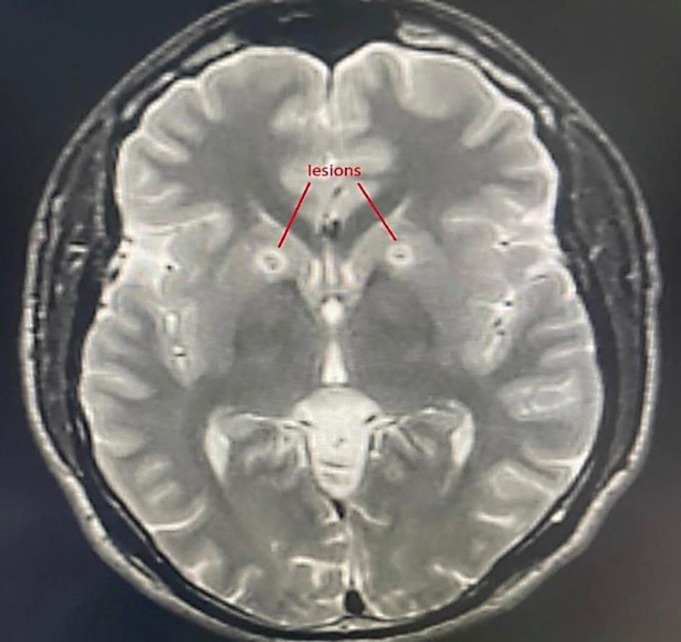

Bilateral anterior capsulotomy in a patient with severe obsessive-compulsive disorder: Case report.

{"title":"Bilateral anterior capsulotomy in a patient with severe obsessive-compulsive disorder: Case report.","authors":"Sajad Shafiee, Abbas Tafakhori, Mohammad Sadra Nemati, Saeed Kargar-Soleimanabad, Sobhan Alipour-Kiasar, Reza Yazdani-Cherati, Ahmadreza Hojati-Marvast, Omid Ahmadvand","doi":"10.18502/cjn.v23i3.17603","DOIUrl":null,"url":null,"abstract":"","PeriodicalId":40077,"journal":{"name":"Current Journal of Neurology","volume":"23 3","pages":"193-196"},"PeriodicalIF":0.5000,"publicationDate":"2024-07-05","publicationTypes":"Journal Article","fieldsOfStudy":null,"isOpenAccess":false,"openAccessPdf":"https://www.ncbi.nlm.nih.gov/pmc/articles/PMC11994058/pdf/","citationCount":"0","resultStr":null,"platform":"Semanticscholar","paperid":null,"PeriodicalName":"Current Journal of Neurology","FirstCategoryId":"1085","ListUrlMain":"https://doi.org/10.18502/cjn.v23i3.17603","RegionNum":0,"RegionCategory":null,"ArticlePicture":[],"TitleCN":null,"AbstractTextCN":null,"PMCID":null,"EPubDate":"","PubModel":"","JCR":"Q4","JCRName":"CLINICAL NEUROLOGY","Score":null,"Total":0}